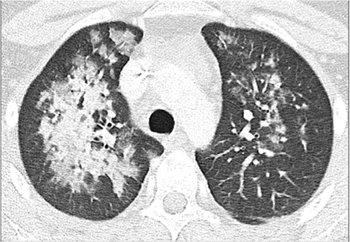

Research reveals lung findings not typically associated with viral pneumonia.

COVID-19 and other viral infections have unique imaging characteristics that can help with diagnosis, experts say.

Expert panel developed six-category system to classify chest CTs and streamline structured reporting around COVID-19.